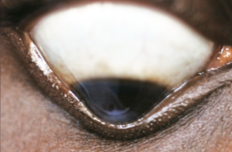

HIDROPS

○ Ocurre por ruptura de Descemet

○ Clínica: córnea toda protruida, cierre palpebral inadecuado, fotofobia, perforación

○ La mayoría quedan en leucoma y terminan en QPP